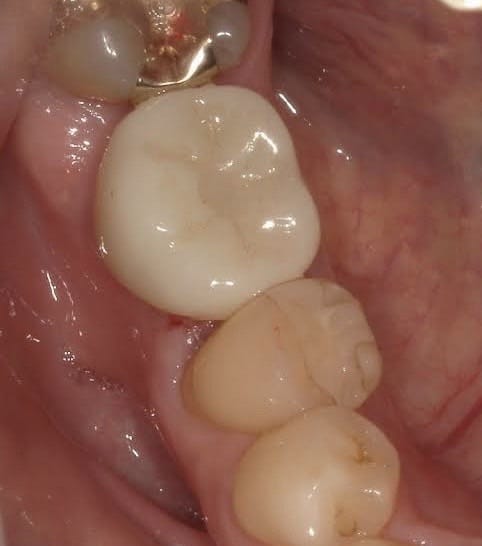

Case011 – インプラント

前医でインプラントの埋入角度が悪く、インプラント周囲炎になってしまった患者様の症例です。

インプラントが虫歯になることはありませんが、インプラント周囲炎というインプラントの歯周病にはなります。

インプラント周囲炎の主な原因は汚れ(菌)と力です。このように斜めに埋入されているインプラントは、真っ直ぐ埋入されているものに比べて汚れも溜まりやすく、噛む力も斜めにかかってしまうため、インプラント周囲炎になるリスクが大幅に高くなります。

この患者様は内側の骨が大幅に溶けてしまっていたので、前のインプラントを撤去して、骨を再生させると同時にインプラントを正しい位置と角度で埋入し直しました。溶けてしまっていた骨が治っていることもレントゲンでご確認いただけるかと思います。

インプラントは「どこの位置にどのような角度で入れるか」によって、一生使い続けられるかどうかの期待値が大きく異なります。値段だけを基準にクリニックを決めるのではなく、信用できる歯医医師と治療を進めることをお勧めします。